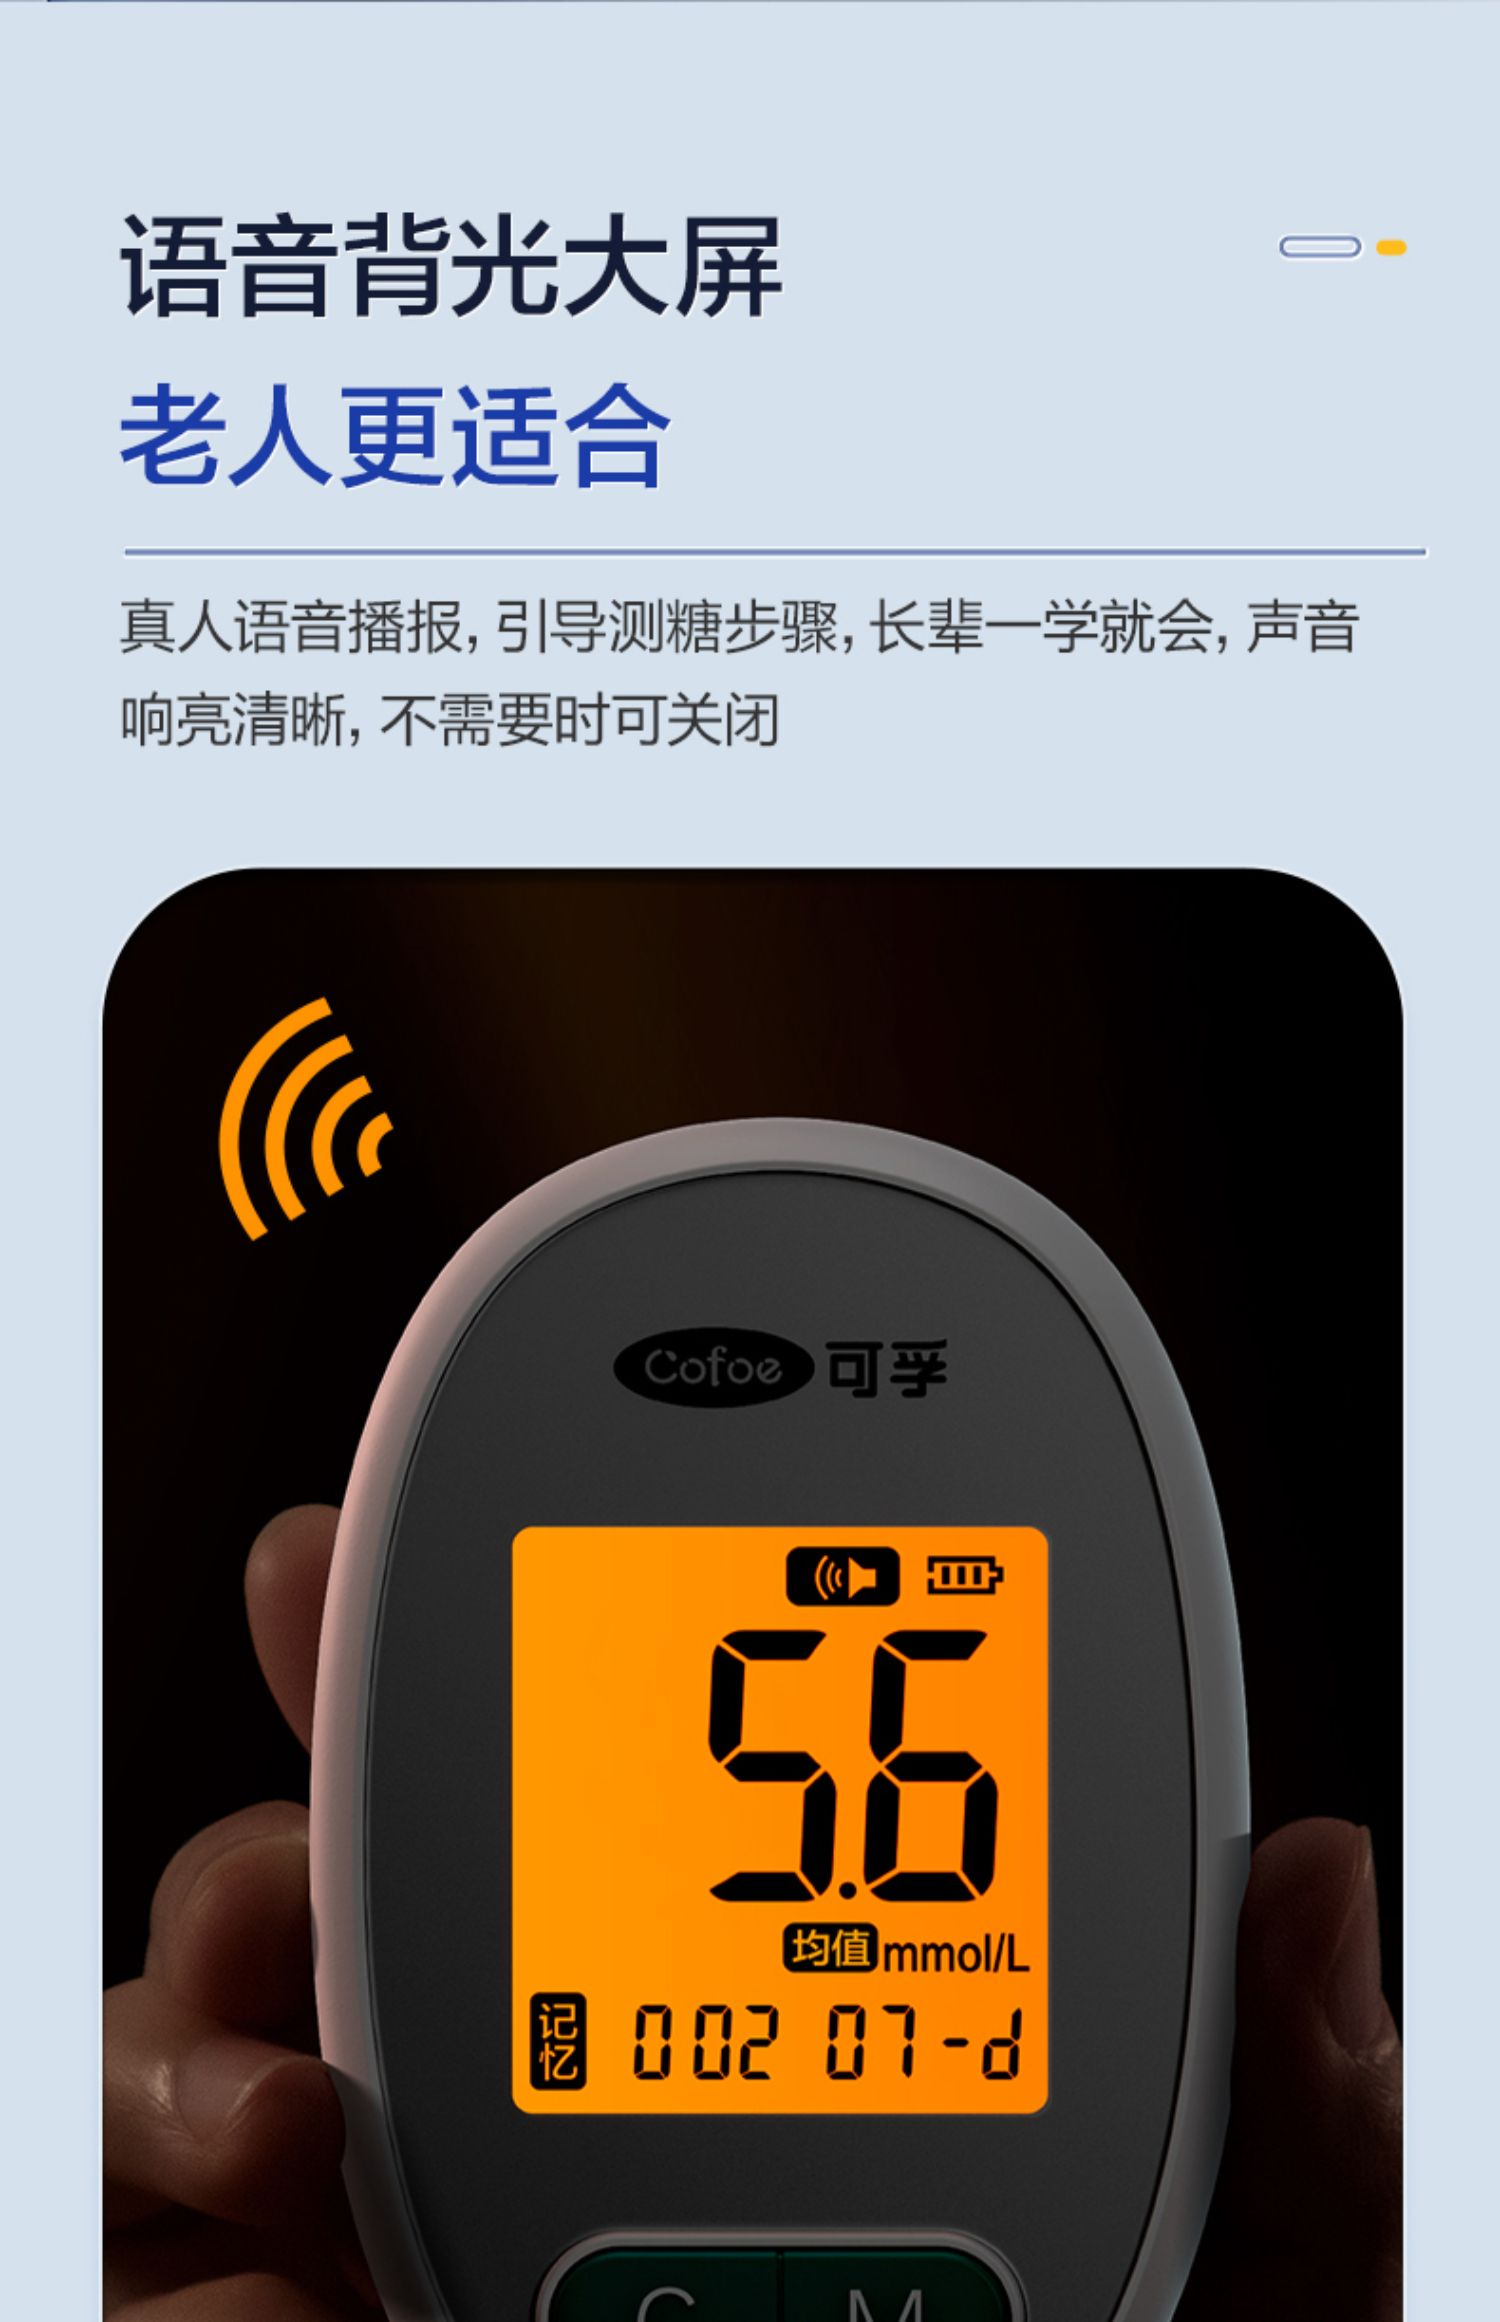

可孚新国标血糖测试仪家用测糖仪试纸官方旗舰店测血糖的仪器孕妇

Фото та опис товару